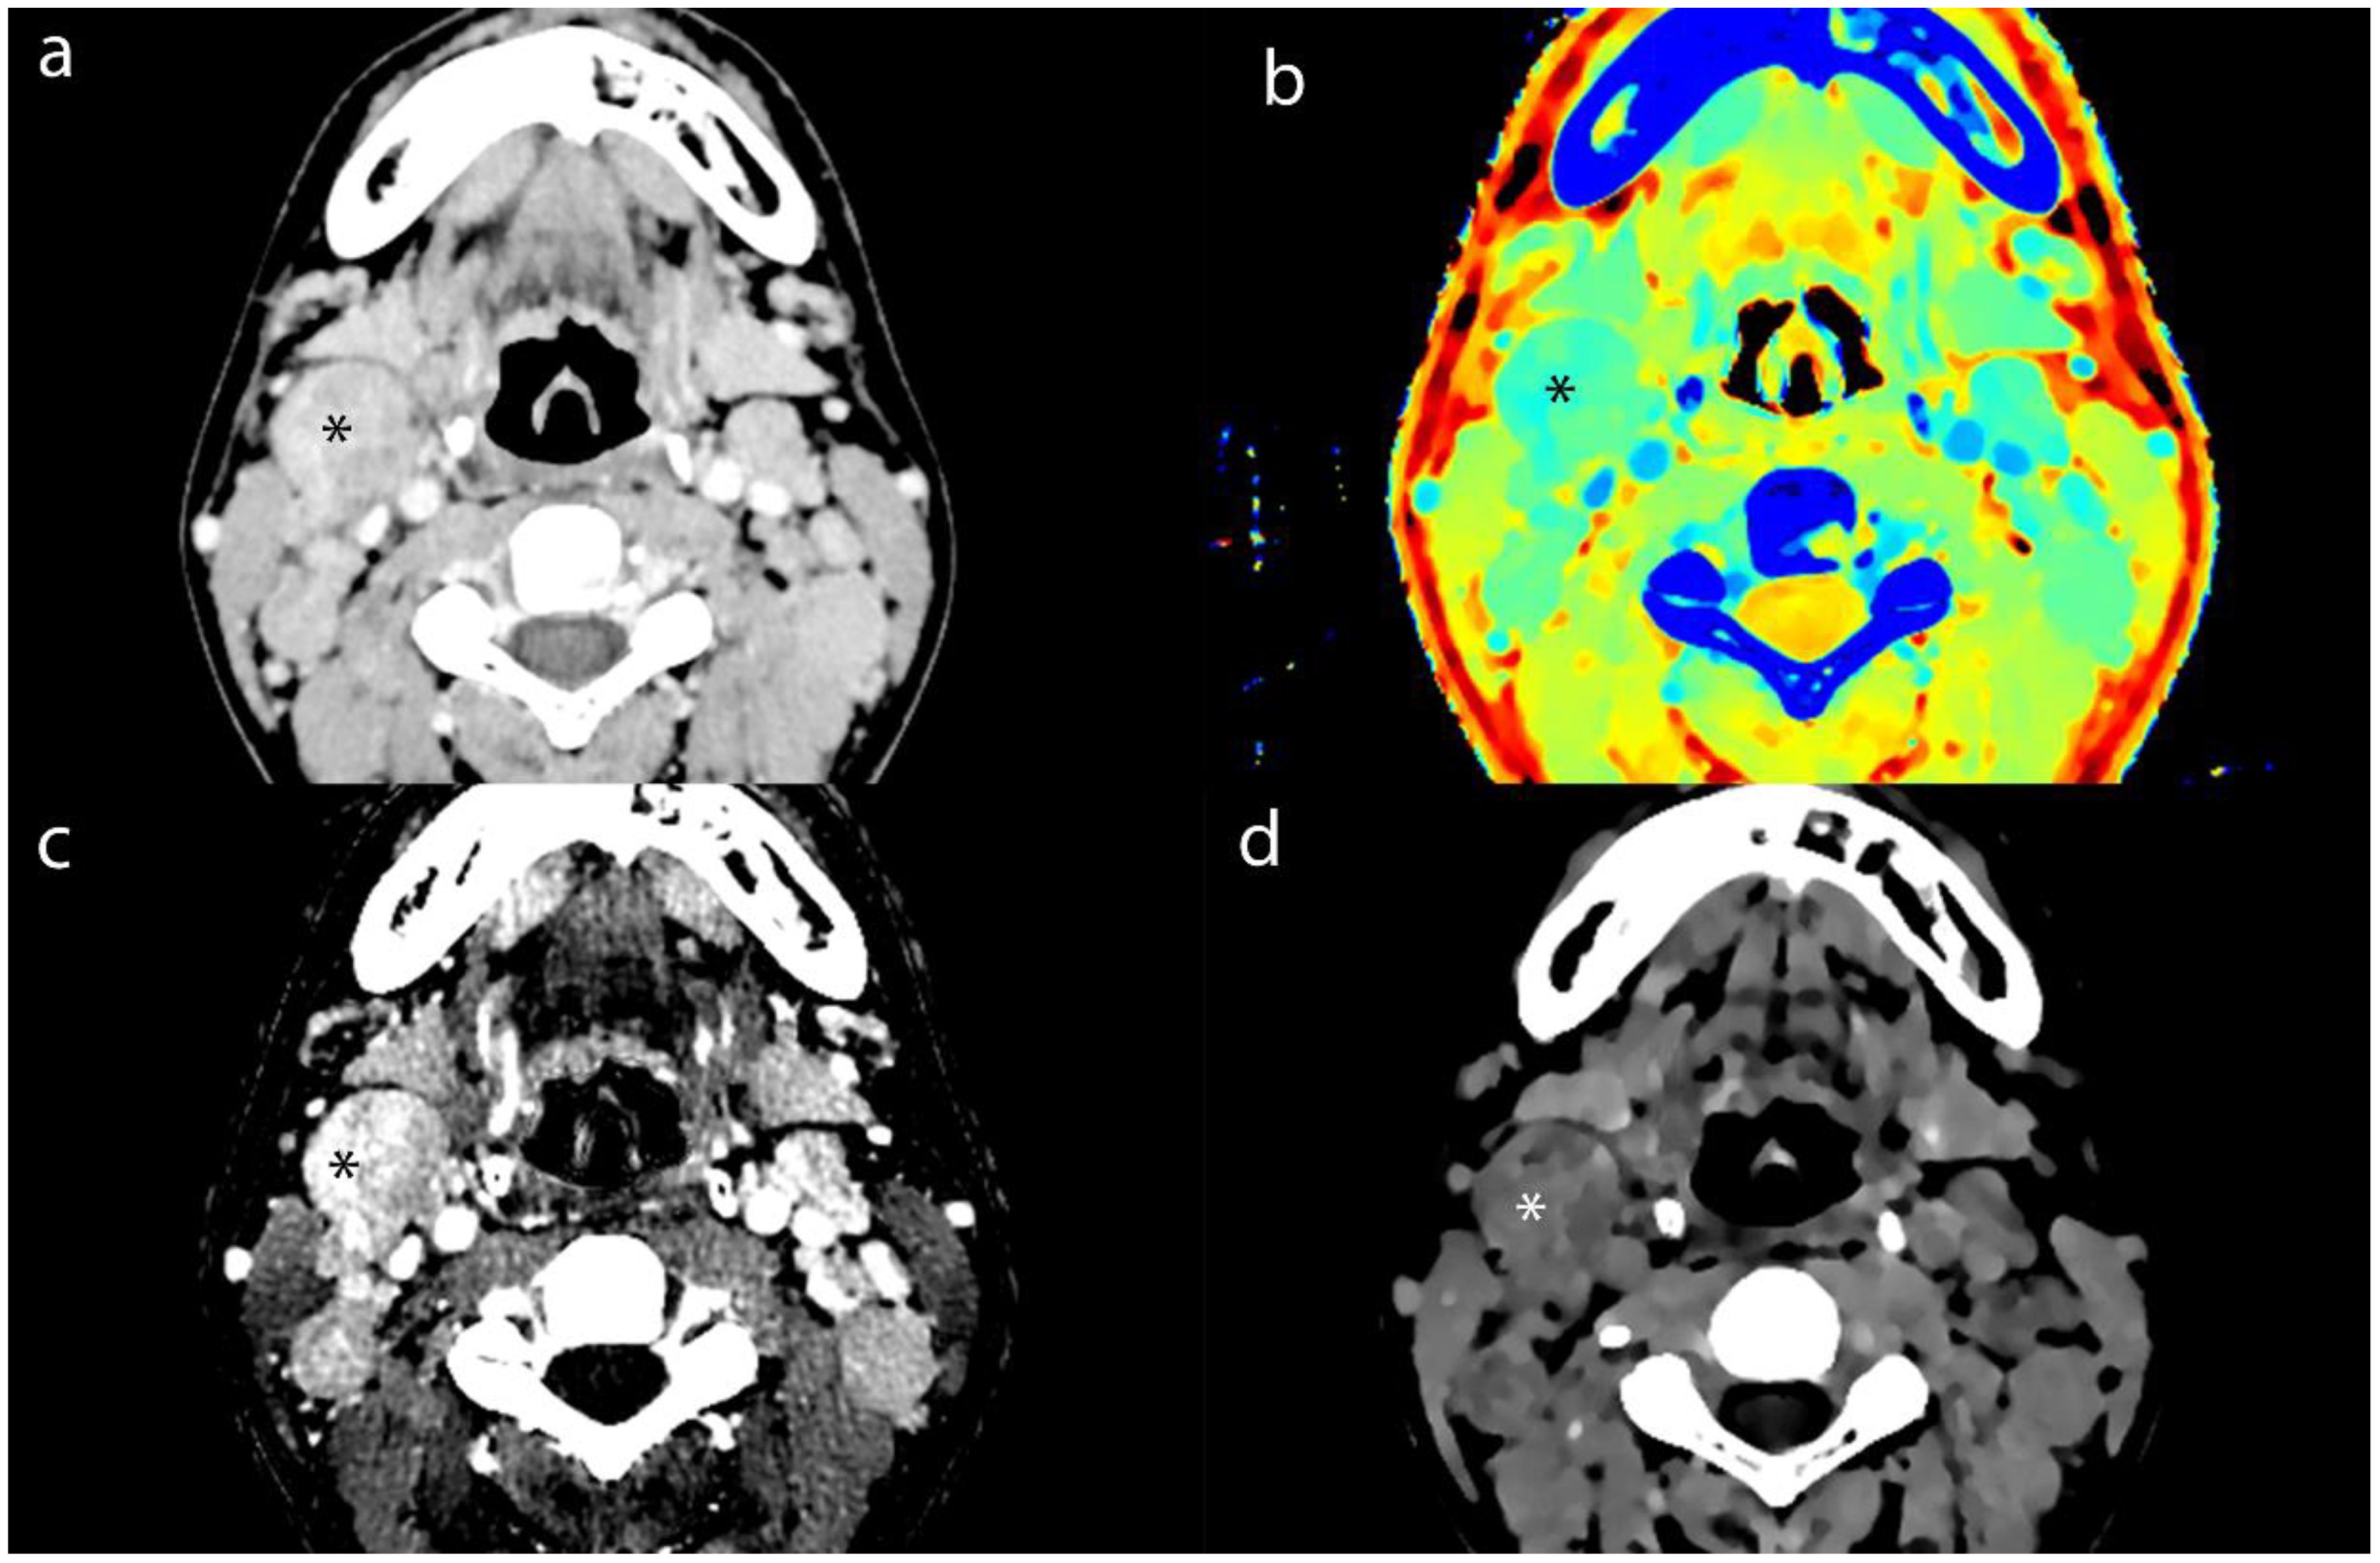

Purpose: To explore the value of dual-energy CT (DECT) in evaluating the efficacy of nasopharyngeal carcinoma (NPC) and in the detection of metastatic lymph nodes (MLNs). Materials and Methods: For this retrospective study, we collected and analyzed clinical and imaging data from 83 patients diagnosed with NPC via histopathology, who were admitted to the Radiotherapy Department from August 2022 to July 2024. The cohort consisted of 64 males and 19 females, with an average age of 50.86±13.45 (years). All patients underwent DECT enhancement and MRI scanning before and after the first treatment course to assess the extent of lesions and lymph nodes (LNs). A total of 423 LN imaging datasets were analyzed. We measured iodine concentration (IC), effective atomic number (Zeff), electron density (ED), and normalized iodine concentration (NIC). Additionally, we recorded the magnetic resonance ADC values of the LNs. Results: Statistical analysis of Zeff, ED, and NIC values of lesion and LNs revealed no significant differences between groups (p > 0.05). The Zeff, ED, and NIC values for lesions and LNs were significantly lower after treatment than before (p < 0.05). Receiver operating characteristic (ROC) analysis for MLNs indicated that the area under the ROC curve (AUC) for NIC indicated high accuracy. Conclusion: DECT provides valuable functional parameters for assessing the efficacy of NPC and demonstrates significant clinical application value. Notably, the NIC parameter shows high diagnostic efficacy for MLNs, comparable to the ADC value obtained from MRI.